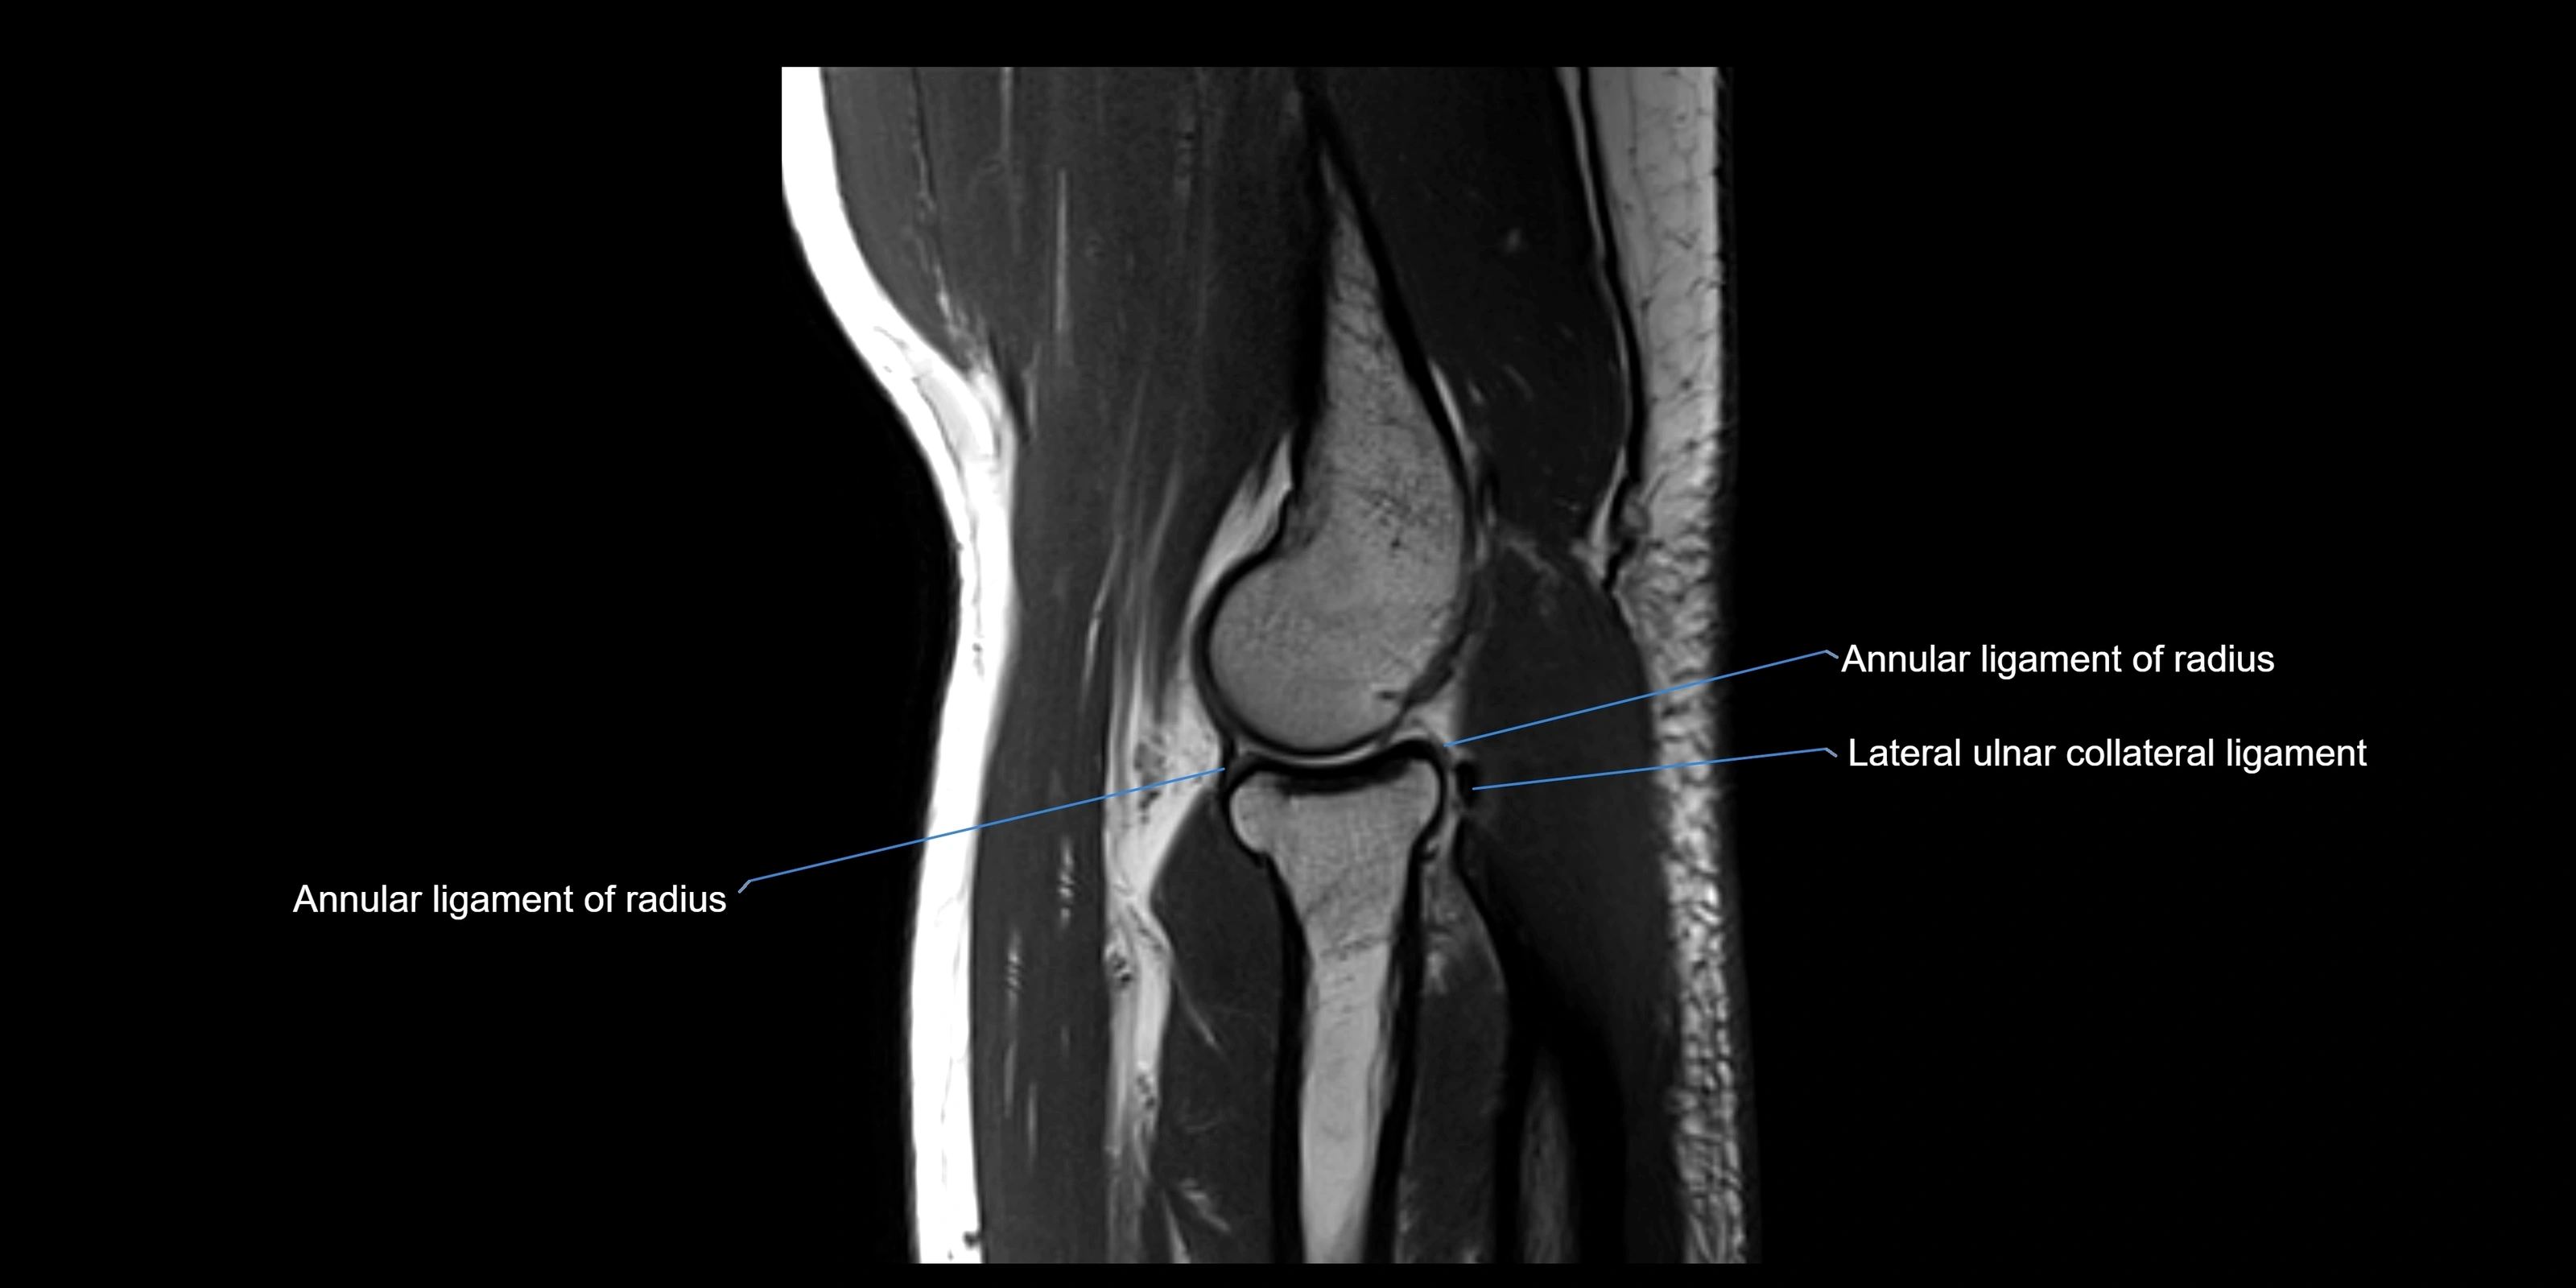

MRI images

image